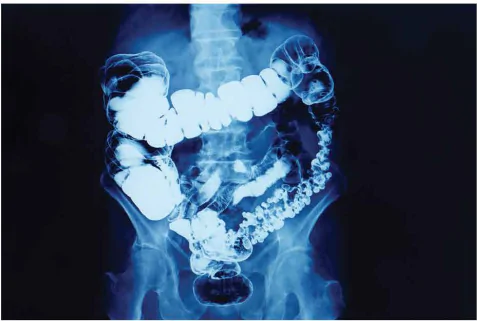

Như chúng ta biết, các mô khác nhau sẽ hiển thị khác nhau trong hình ảnh X-quang. Xương có thể dễ dàng phân biệt với mô mềm (chẳng hạn như cơ) vì xương là một chất hấp thụ tốt tia X. Tuy nhiên, bác sĩ luôn mong muốn phân biệt được hình ảnh của các bộ phận khác nhau nhưng có khả năng hấp thụ tia X như nhau. Để làm được điều này, người ta sử dụng hoá chất để tạo ra sự tương phản. Đối với chụp X-quang, thông thường người ta có thể sử dụng iodine hoặc barium là những chất hấp thụ tốt tia X. Bệnh nhân có thể được cho uống chất lỏng chứa barium hoặc tiêm chất lỏng tương tự vào mô của vị trí cần chụp. Các mô này sau khi được tiêm chất lỏng chứa barium sẽ hấp thụ tia X tốt hơn, do vậy biên của các mô này sẽ hiển thị rõ ràng hơn trên hình ảnh. Hình 6.8 là hình ảnh chụp X-quang ruột của một bệnh nhân sau khi được cho uống barium.

Hình 6.8. Hình ảnh X–quang ruột của bệnh nhân sau khi sử dụng barium. Hình ảnh này cũng đã được xử lí để làm nổi bật các đặc điểm cần quan tâm